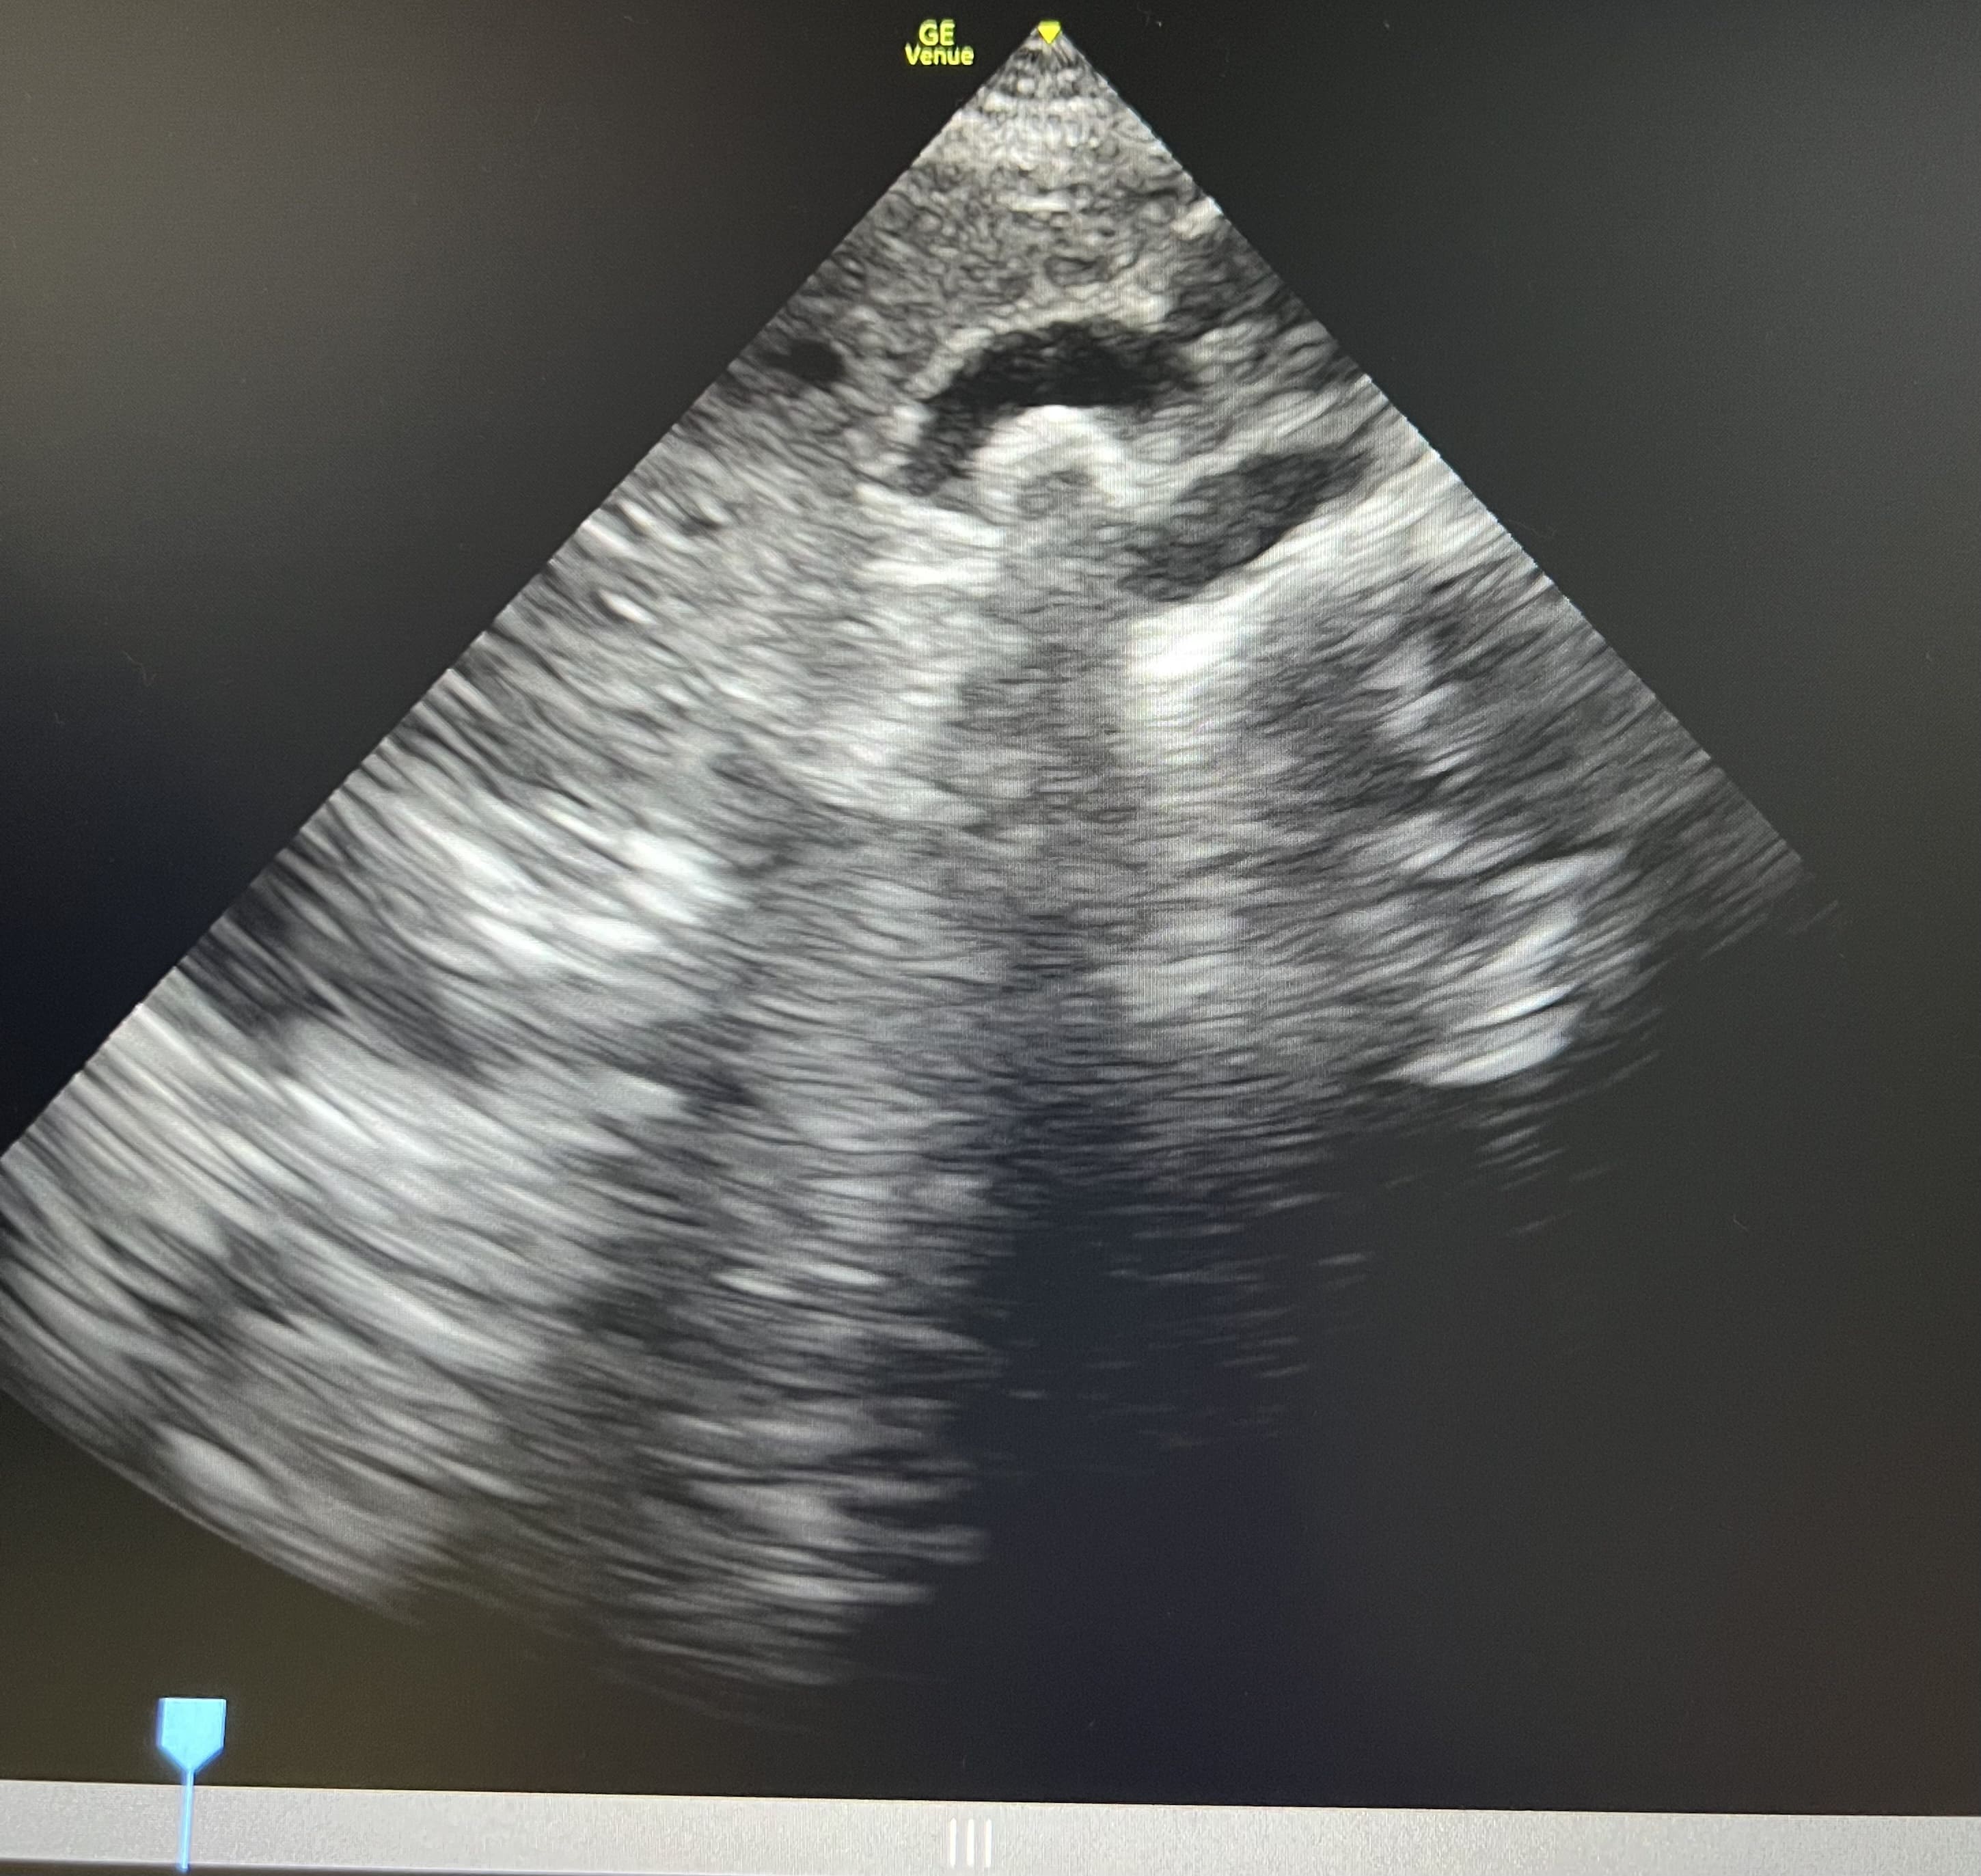

Pruebas complementarias: Ecografía abdominal con sonda convexa: vesícula biliar distendida con litiasis de 4 centímetros en su interior y sombra acústica posterior. Ecografía con sonda lineal en flanco derecho: lesión anecoica ovalada con imagen hiperecoica en su interior, que no captan Doppler, y movilizan con la respiración, en tejido subcutáneo.